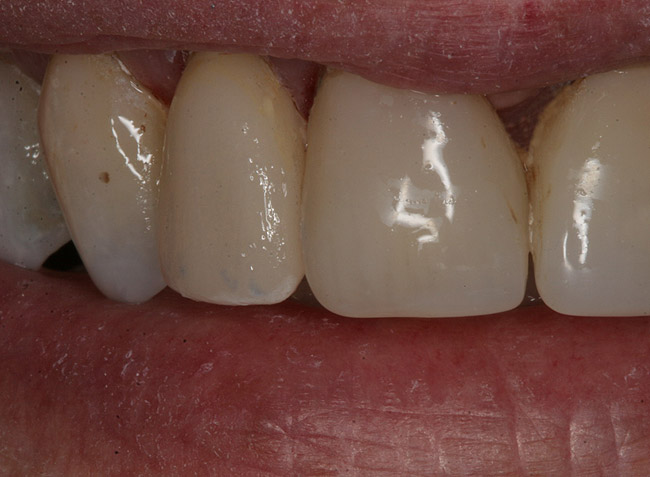

Figure 18  Postoperative view of the single-visit crown.

Figure 18